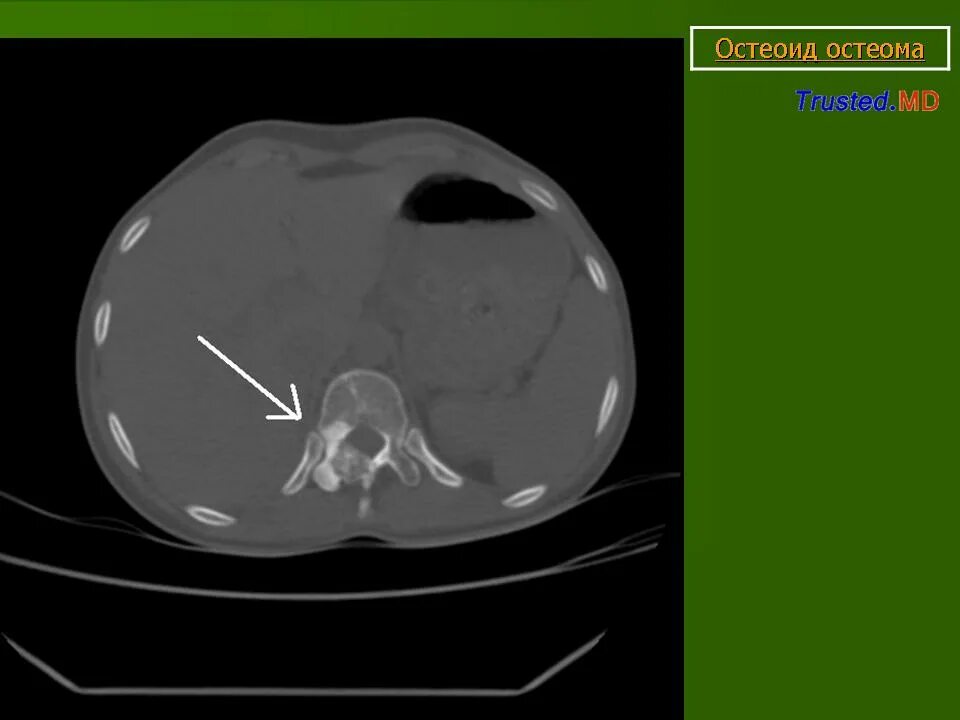

Остеома мрт